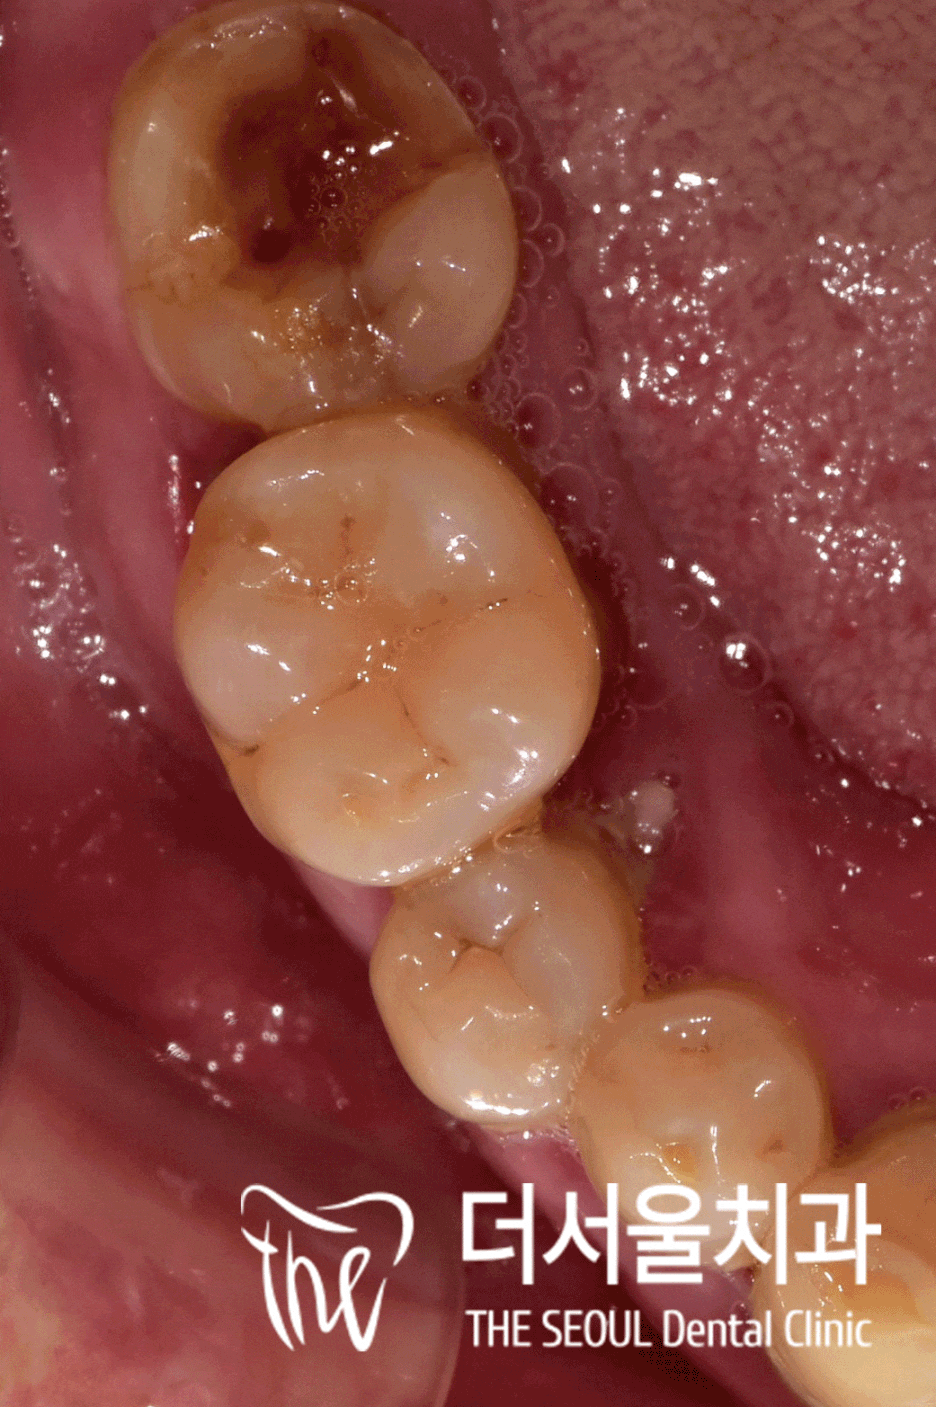

환자의 구강 내를 살펴봤는데요.

네.. 일단 전반적으로 상황이 좋지 않네요.

군데군데 썩어있는 치아들과

홀랑 빠져버린 곳 그리고 정출까지..

위쪽은 누가 봐도 골소실이 심해 보였는데요.